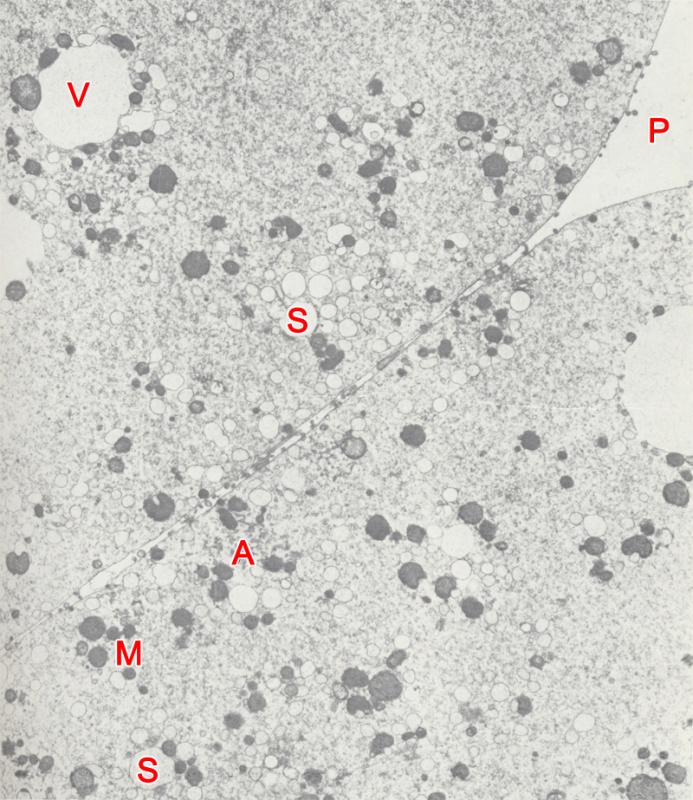

TEM of the cytoplasm and cell junction of a stage 2, 2-cell embryo in vitro, 44 hours post-insemination, (original magnification x8,400). Each blastomere has most of the organelles found in oocytes and 1-cell embryos. The blastomeres are closely apposed and the intercellular space contains microvilli that are sometimes aligned longitudinally or interlock with one another. Mictochondria (M), vesicular smooth endoplasmic reticulum (S) and small aggregates of smooth endoplasmic reticulum (A) are distributed randomly in the cytoplasm. Some parts of the vesicular smooth endoplasmic reticulum are dilated and translucent. Large vacuoles (V) are associated with mitochondria.

SS = subzonal space

Keywords: blastomere, cell junction, cytoplasm, intercellular space, microvilli, mitochondria, oocyte, stage 2 embryo, subzonal space, two-cell embryo, vacuole(s), vesicular smooth endoplasmic reticulum